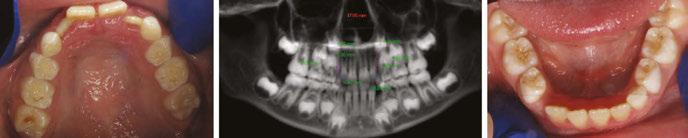

A pediatric-patient dedicated Sleep Medicine laboratory setting is difficult or impossible to find, setting aside what is considered the diagnostic gold standard, overnight PSG. Most screening questionnaires can be valuable as SRBD morbidity assessment tools and reliable for predicting increased risk. They are based solely upon identifying SRBD behavioral phenotypes known to be associated with suboptimal sleep hygiene (e.g., snoring, teeth grinding/bruxism, excessive bodily movements). The Sleep Clinical Record (SCR)15 is an exception because it relies on not only behavioral morbidity traits, but also some physical morbidity traits such as constrictive/retrusive and retrognathic jaw maldevelopments,16 which are known to be associated comorbidities with SRBD.17 Most of these physical traits can be classified as malocclusion phenotypes and generally are located within the interconnected craniofacial respiratory complex (CFRC)18 (Fig. 1) which was foreshadowed by Dr. LeRoy Johnson in the opening paragraph of

this review: ‘The face has evolved with the functions of mastication and respiration.’- L.J. 1921.

While the SCR goes further than most other screening assessment tools towards identification of some CFRC/SRBD co-morbidities, it is limited in its comprehensiveness. Ideally, in addition to screening for birth/perinatal history risk factors, such as pre-term birth,19,20 clinicians should have validated screening tools for identifying behavioral comorbidity traits, and for identification of physical risk phenotypes of the CFRC. The CHICAGO HEARTS screening tool combines these survey areas. (Fig. 2).

In a lecture held in 2018 at Boston University entitled ‘Sleep Disordered Breathing/Obstructive Sleep Apnea Symposium’,21 a new screening tool called C.H.I.C.A.G.O. H.E.A.R.T.S. (C.H.) had been introduced as potentially becoming the first validated screening device specifically designed to identify CFRC physical traits that can often be comorbid with SRBD. Several of these traits are listed within the C.H. acronym (Fig. 2). For instance, under the first letter ‘C’ are listed: Crossbite 22,23 Fig. 3 and Crowded Pharynx;24,25 ‘H’: Hyper-divergent growth (Fig. 4),16 Hypertrophic tonsils and/or adenoids;26,27 ‘I’: Incompetent lips;28 ‘C’: Constricted arches (Fig. 5);23,29,30 ‘A’: Airway anatomy (Fig. 6);22,31 ‘G’: Grinding teeth (bruxism)32 and Gonial angle excess;33 ‘O’: Overweight child34 and Obtuse nose-lip angle( NLA);35 ‘H’: Highly-vaulted palate;36 ‘E’: Ezcema-atopia37 and Eye appearance-venous pooling38 and scleral show;39 ‘A’: Anterior open-bite

(Fig. 8):40 ‘R’: Retrognathia (Fig. 9) (mandible16 and/or maxilla);41 ‘T’: Tongue posture,42 tie (tether),43,44 scalloping;45 ‘S’: Septal deviation46 and night Sweats (diaphoresis).47